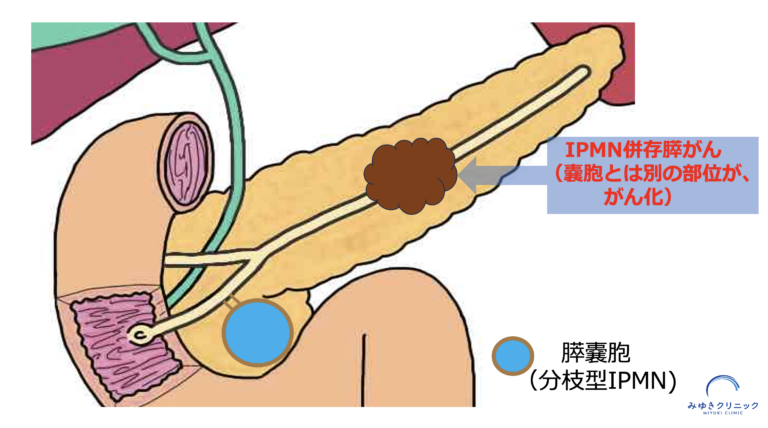

IPMNに関連する膵がんには、

IPMNとは別の場所に発生するタイプ(IPMN併存膵がん)の2種類があります - 特にIPMN併存膵がんは、嚢胞の大きさに関係なく発生することがあります

IPMNとは別の場所に新たに膵がんが発生する「IPMN併存膵がん」

もうひとつは、IPMNとは別の場所に新たに発生する「併存膵がん」です。

このように、IPMNがある場合は、嚢胞の変化だけでなく、膵臓全体を丁寧に評価することが重要になります。

IPMNの経過観察中に、嚢胞とは別の場所に膵がんが見つかった症例があります(IPMN併存膵がん)。

このように、IPMNがある場合は嚢胞の変化だけでなく、膵臓全体に新たに膵がんが発生することがあります。